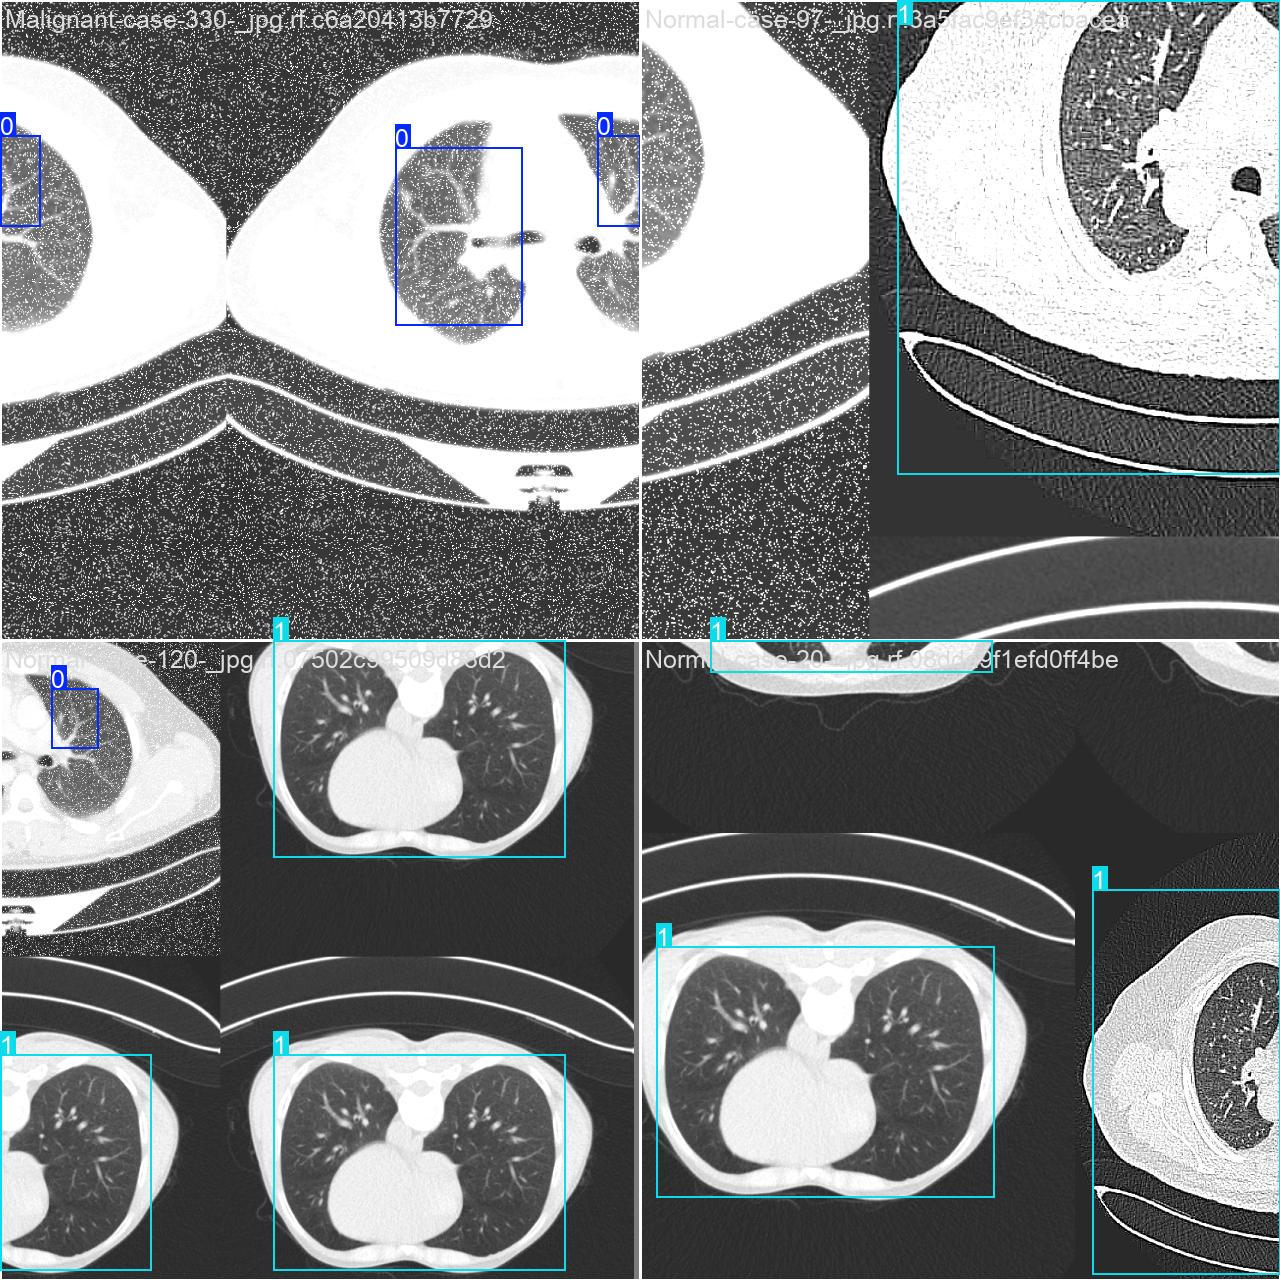

部分数据集图像如下图所示:

部分标注如下图所示:

这种数据分布方式保证了数据在模型训练、验证和测试阶段的均衡性,为 YOLOv8n 模型的开发与性能评估奠定了坚实基础。